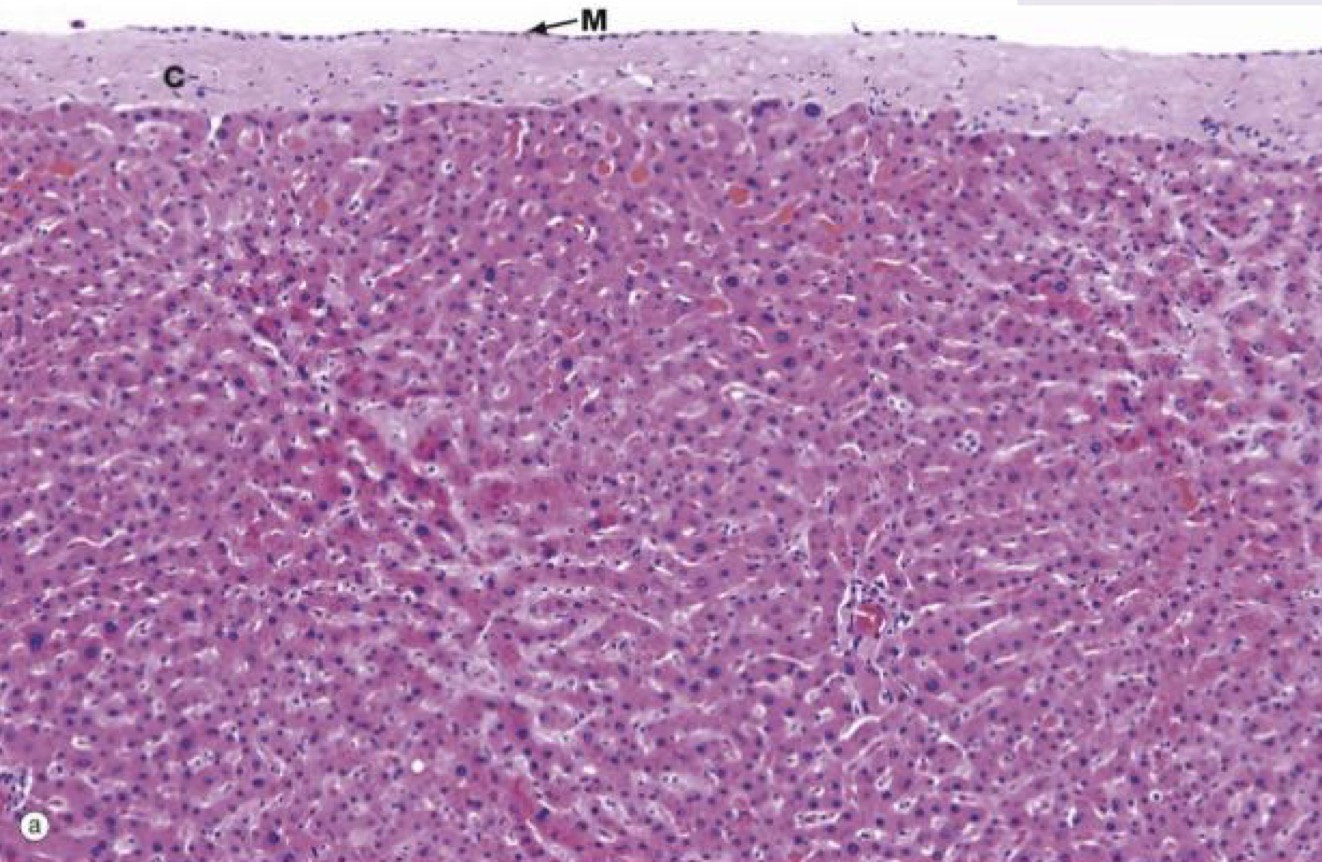

Identify the Organ and Structures?

Liver; Mesothelium, Hepato, Sinu